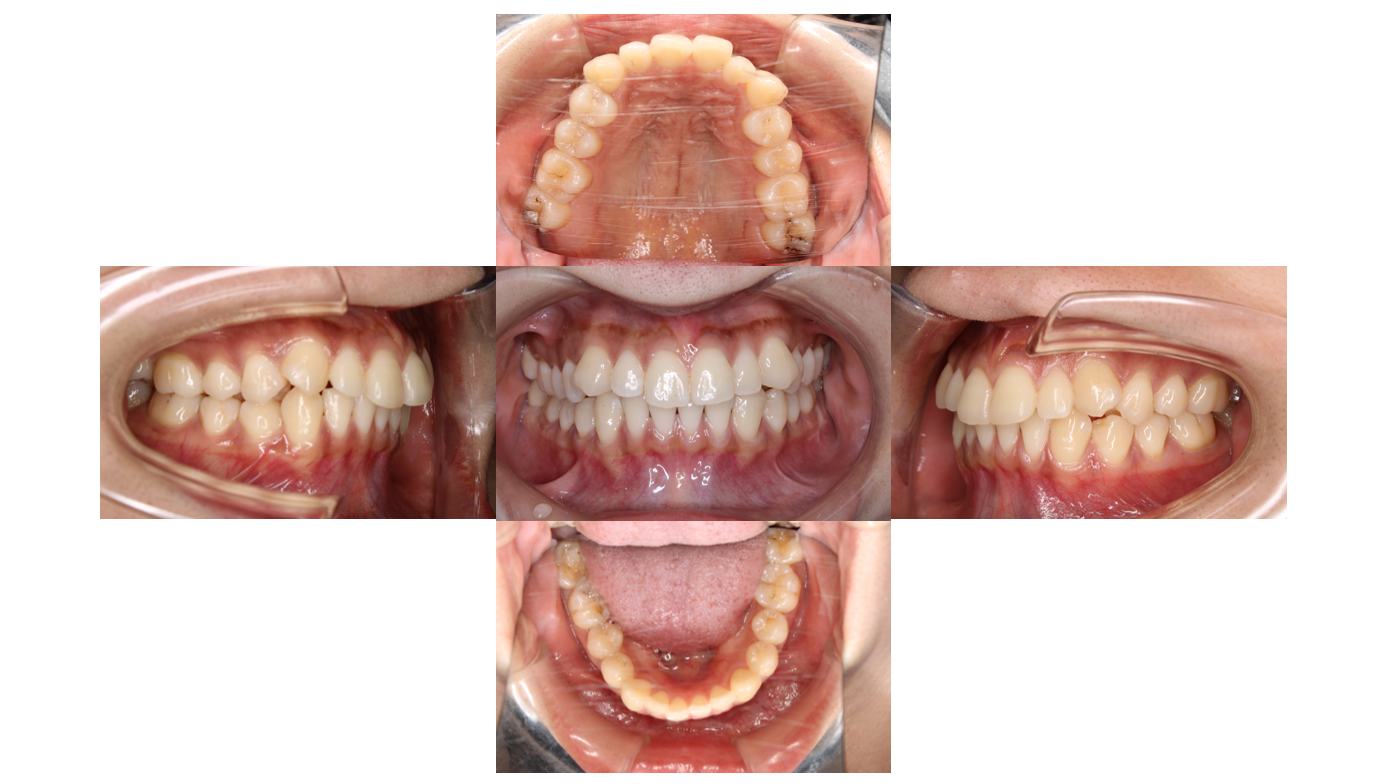

After

1年2か月経過

歯の表面にボタンを付けて噛み合わせを整えます

1年6か月経過

上下とも全体的にゴムをかけて隙間が空いてこないようにします